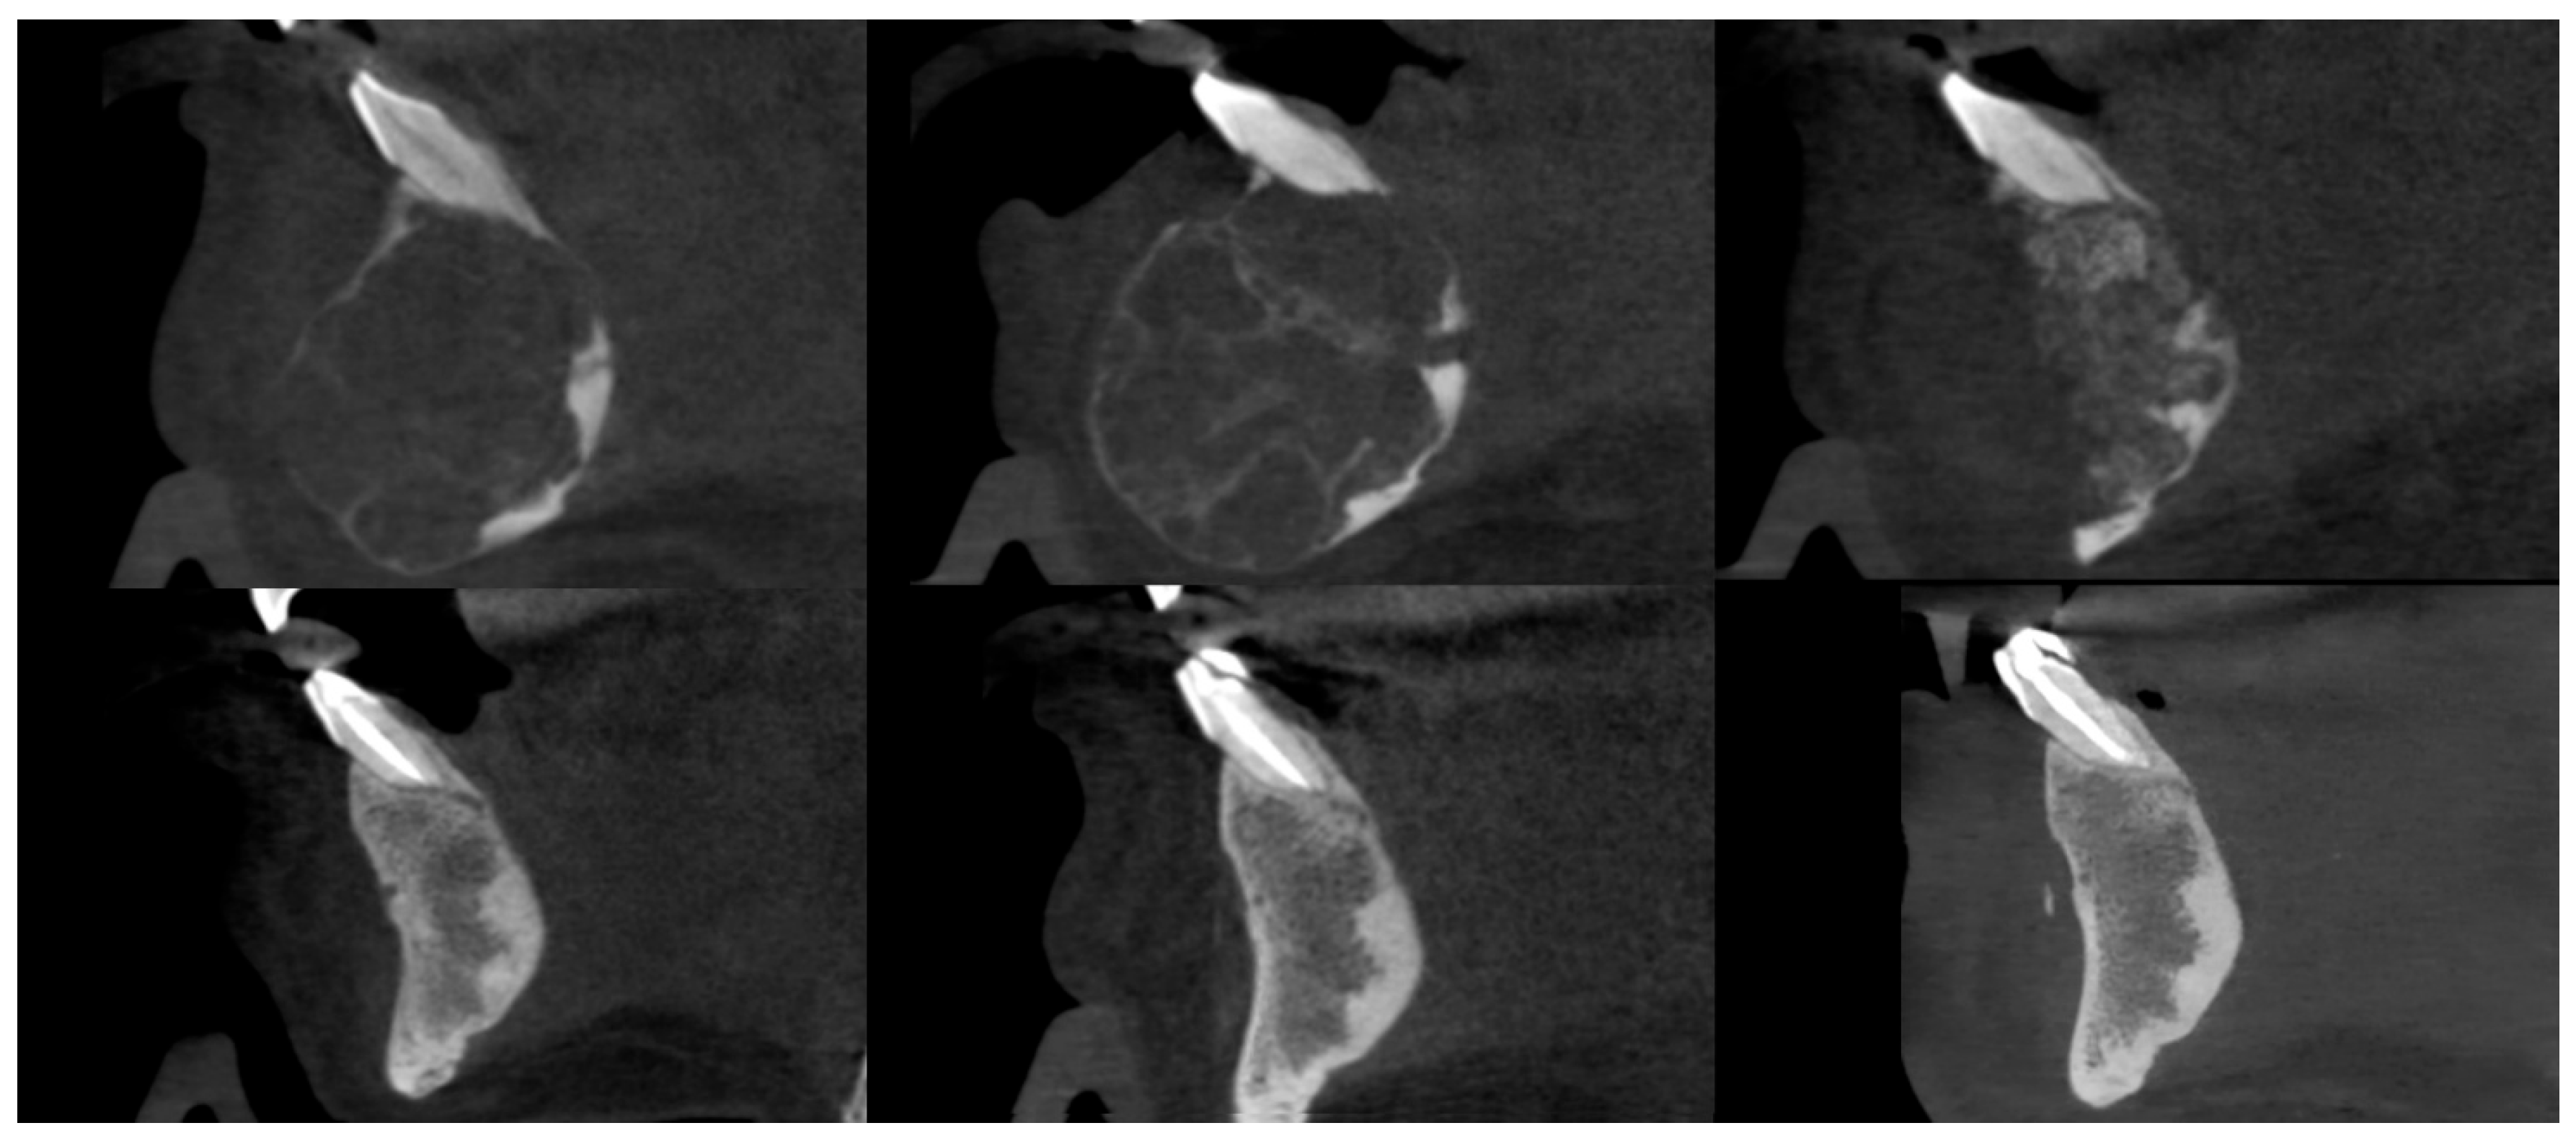

3.3. Osteosclerotic Rim (Peripheral Corticalization)

3.4. Complications During Treatment

3.5. Recurrence